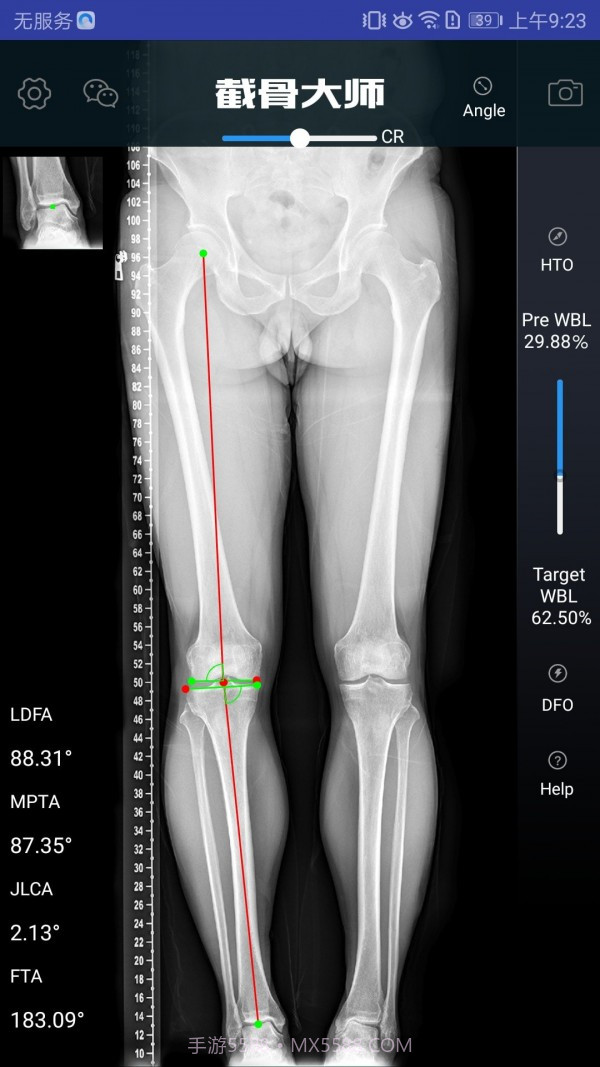

截骨大师真的估计是个宝藏APP,特别适合骨科医生和医疗人员使用。它的手术模拟功能超级高效,能让医生在手术前清晰地了解手术效果,避免在实际操作中出现失误。而且,它的参数计算非常精准,真的估计是为医生的工作提供了很大的帮助。用这款软件,你不仅能节省大量准备时间,还能显著提高手术的成功率,对患者的治疗也有很大保障。作为医生,这款工具简直估计是必不可少的选择!

软件截图